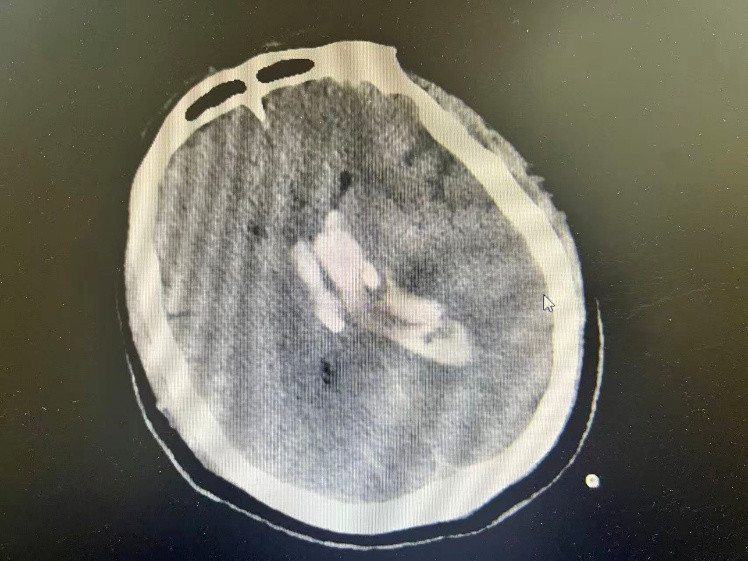

神经外科陈楠主任医师迅速到位,全面评估后明确手术指征。在多科室紧密配合下,于12月9日凌晨为患者实施急诊“双侧脑室钻孔引流术”。手术过程顺利,术后患者转入ICU监护治疗。

图2

(配图说明:图1-2为术前颅脑CT,显示脑室系统血肿铸型;图3为术后复查CT,显示引流管位置良好;图4为手术团队术中操作场景。)